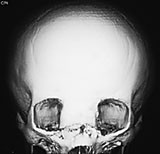

Cerebral CT med 3D-rekonstruksjon samt cerebral MR viste defekt mellom os frontale og os nasale, en stor og dyp utvidelse av fremre skallegrop og utvidelse av intrakraniale hulrom.